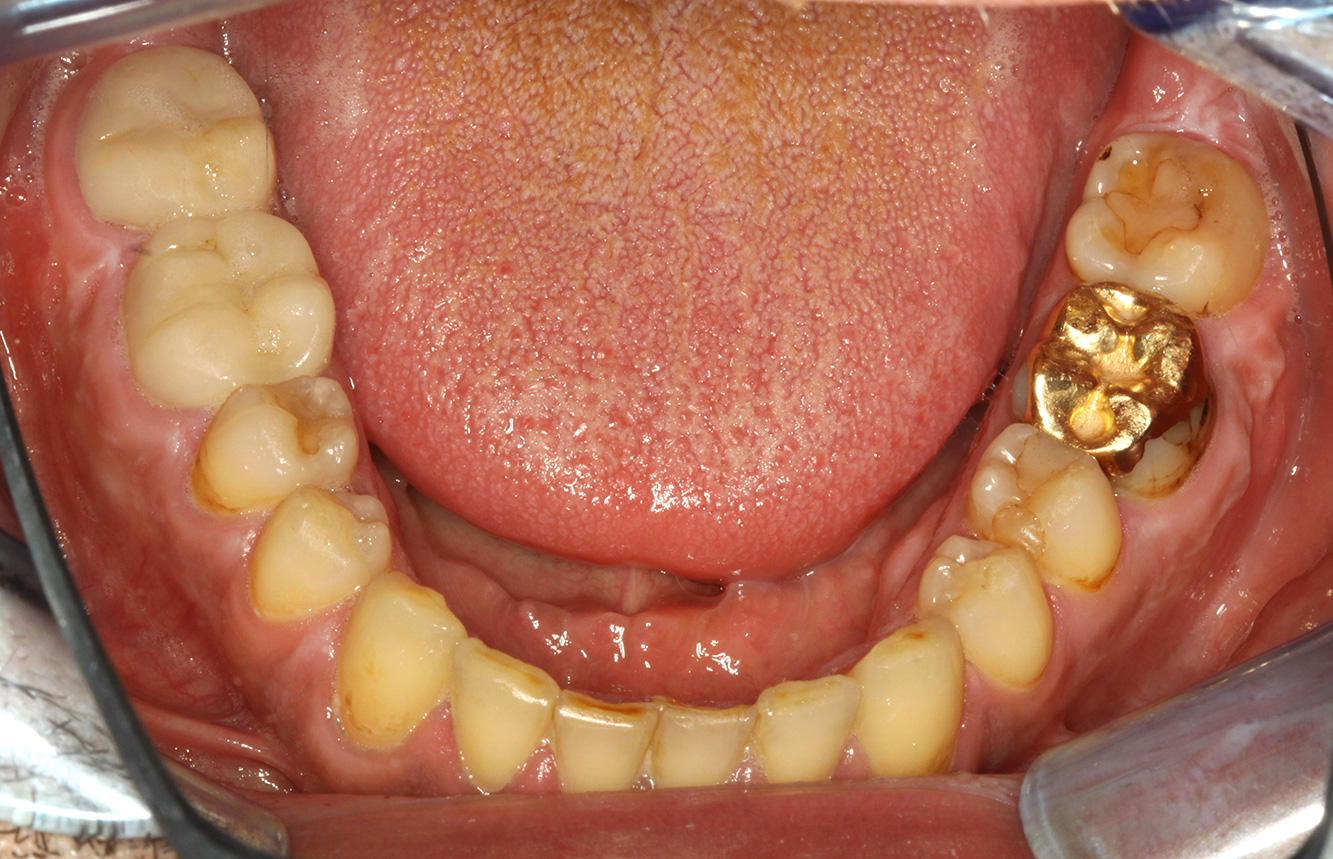

Foto: © Dr G. Schmalz y Dr D. Ziebolz MSc

Il paziente ha 39 anni e in passato è stato sottoposto ad un intervento per la sostituzione della valvola aortica dovuta a insufficienza valvolare ed endocardite. Assume regolarmente l'ASS 100 come anticoagulante. Per quel che riguarda lo stile di vita, il regime alimentare seguito dal paziente è classificato come “dieta che favorisce la formazione della carie”, per via del consumo regolare di cibi ad alto contenuto di zuccheri e dei sei-sette pasti consumati al giorno. La salute orale del paziente indica un rischio moderato di carie, con lesioni attive. Il rischio di parodontite è basso, tuttavia il paziente è affetto da gengivite. Si formulano quindi i seguenti consigli per il trattamento di profilassi.